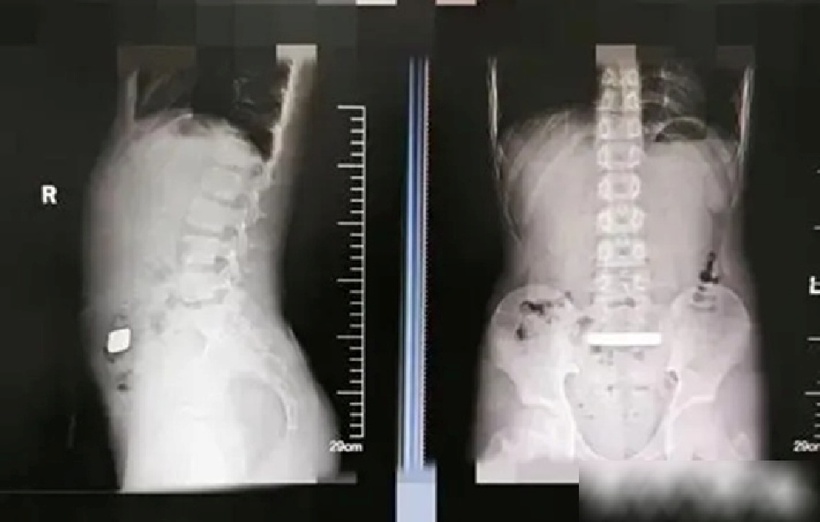

Bác sĩ phát hiện một vật kim loại rất đặc mắc kẹt trong đường tiêu hóa của bệnh nhi. Ảnh: QQ.

Theo Tạp chí Thanh niên Việt, cậu bé 11 tuổi Tiểu Thiến ở Tô Châu (Trung Quốc) cảm thấy bụng hơi căng, nhưng không thấy đau dữ dội hay khó chịu gì khác. Phát hiện sự việc, cha mẹ đã ngay lập tức đưa cậu đến bệnh viện để điều trị. Sau khi chụp X-quang, bác sĩ phát hiện một vật kim loại rất đặc mắc kẹt trong đường tiêu hóa của bệnh nhi. Kết hợp với bệnh sử, Tiểu Thiến được chẩn đoán mắc "vật thể lạ trong đường tiêu hóa".

Do kích thước lớn của vật thể lạ - một thỏi vàng - các bác sĩ lo ngại nguy cơ tắc ruột và tổn thương niêm mạc nên đã nhanh chóng chuyển Tiểu Thiến đến khoa phẫu thuật tổng quát để theo dõi và điều trị.